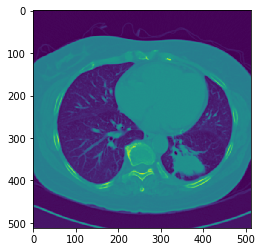

ちゃんとロードできているか確認します。

(スライシングは以下で良いが、ピクセルの並びはitkImage(x,y)に対してnumpy.adarray(h,w)になる)

ndImg = sitk.GetArrayFromImage(image)

ndLbl = sitk.GetArrayFromImage(mask)

plt.imshow(ndImg[24])

plt.show()

plt.imshow(ndLbl[24])

このデータは、3Dのデータになっています。2D画像がZ軸方向に並んでいるので。

pyradiomicsは最初から3Dの計算が想定されているところがすごいと、個人的には思います。